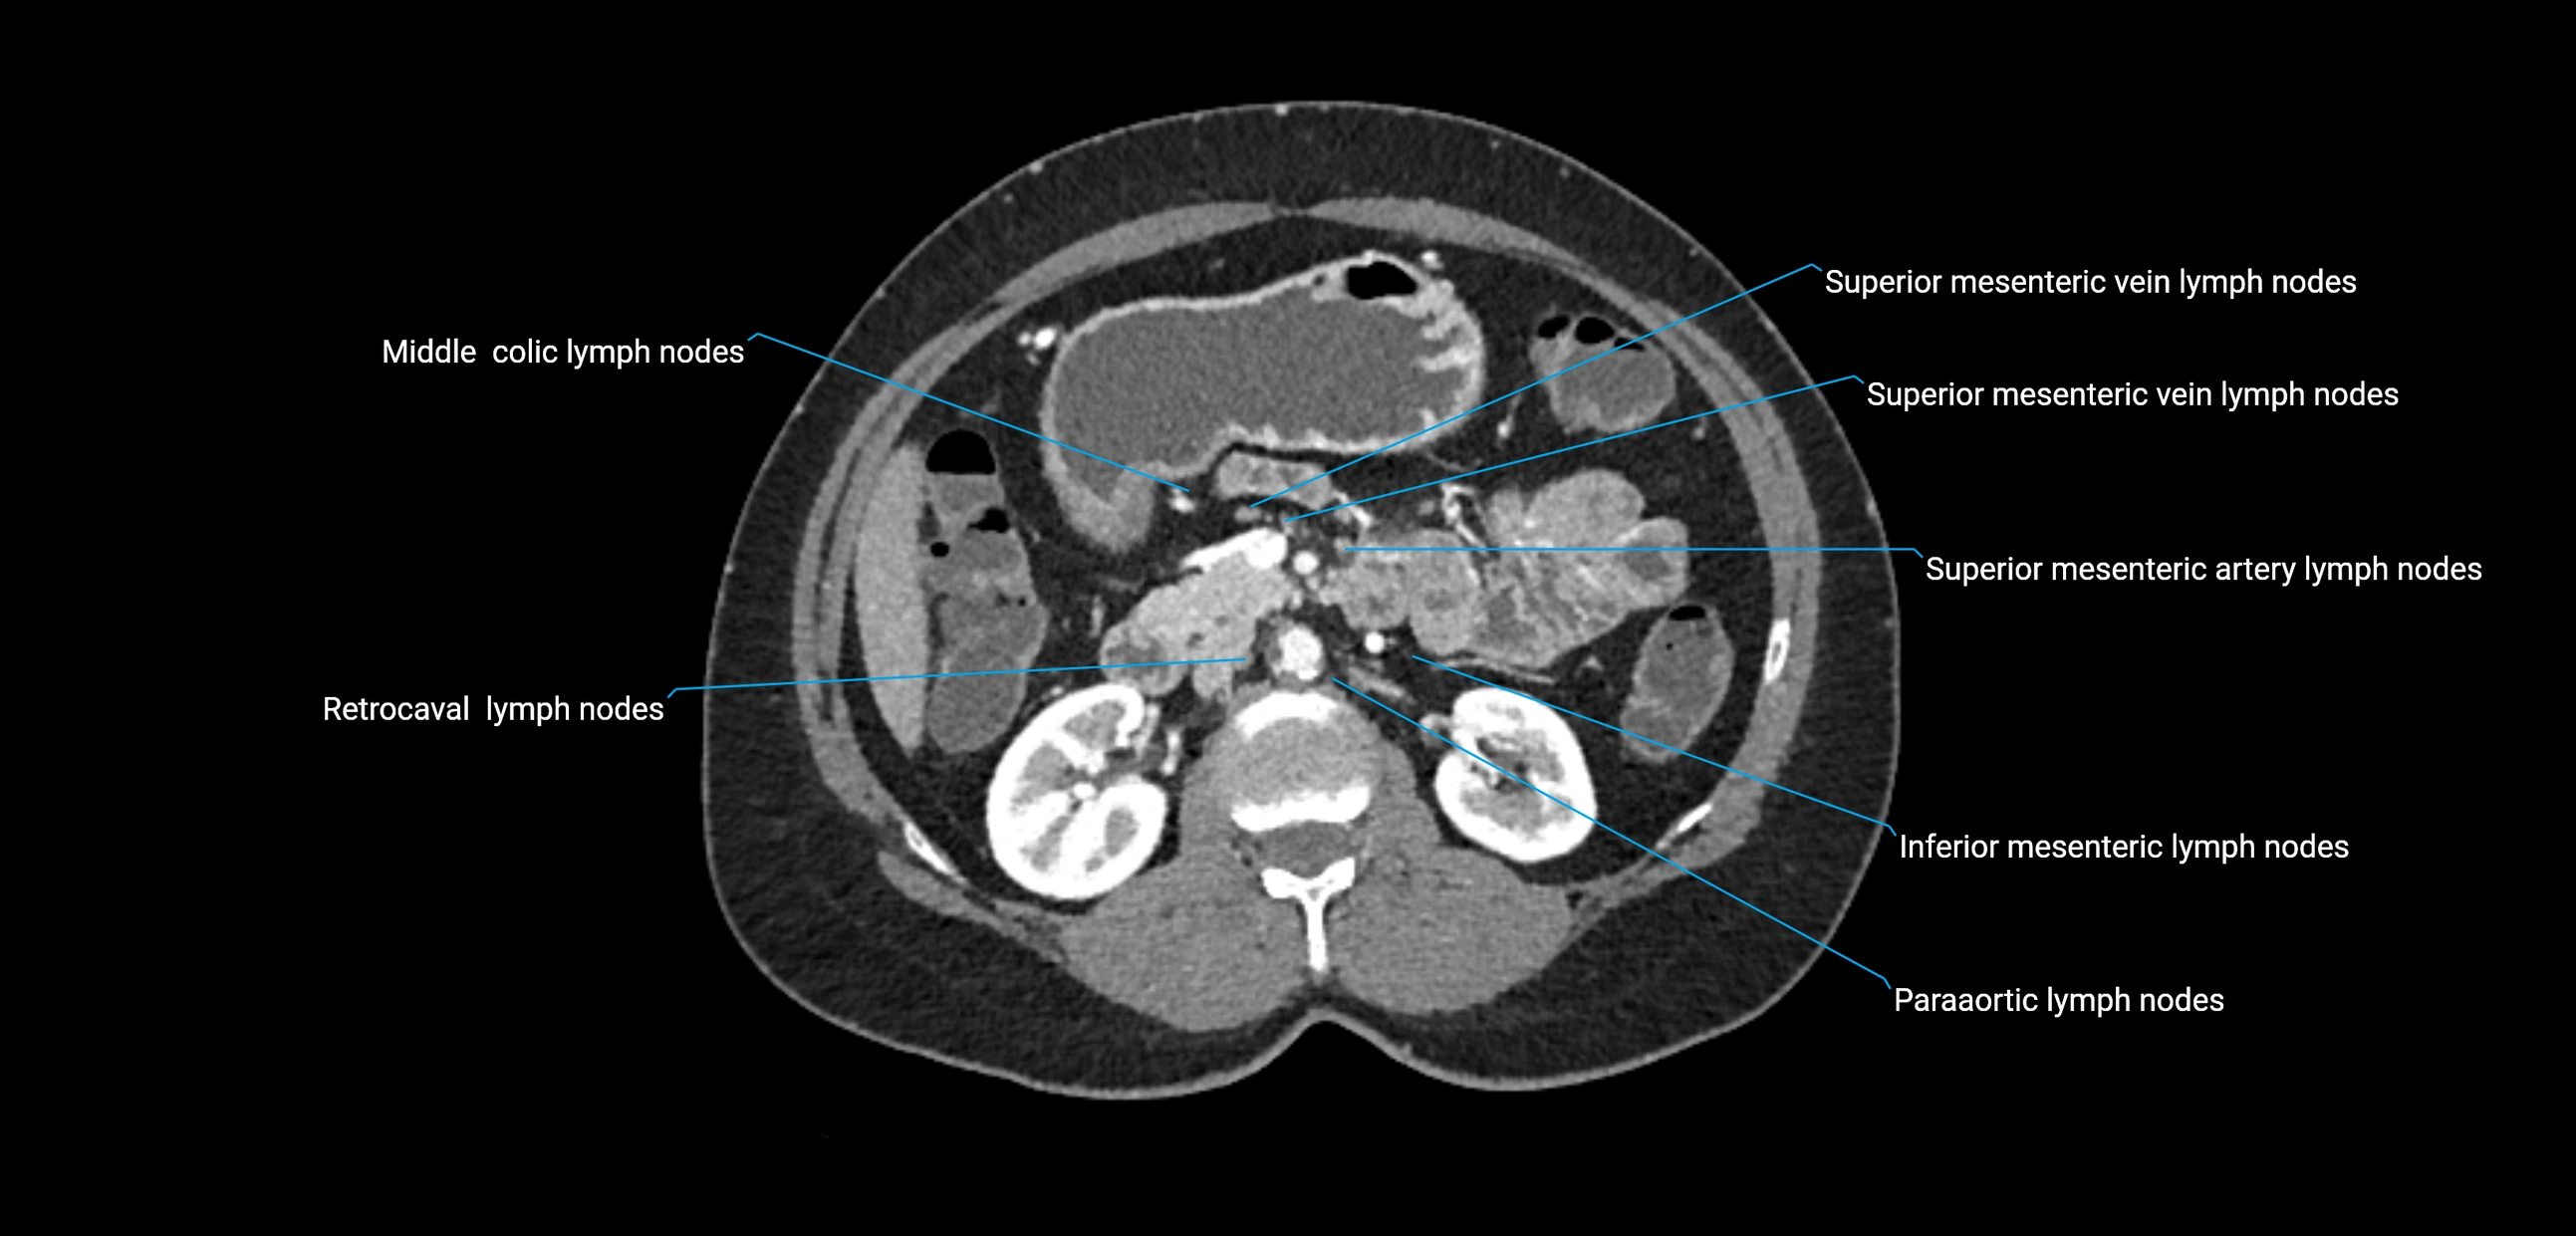

CT Appearance

CT Post-Contrast:

• Normal nodes enhance homogeneously

• Malignant nodes may show heterogeneous enhancement, central necrosis, or conglomerate formation

• Size >1 cm short axis is suspicious, though morphology and distribution are equally important

CT Venography (CTV):

• Demonstrates nodal encasement or compression of adjacent vessels (aorta, IVC, renal veins)

• Useful in staging testicular and ovarian malignancies

• Provides 3D reconstructions for retroperitoneal lymph node dissection planning